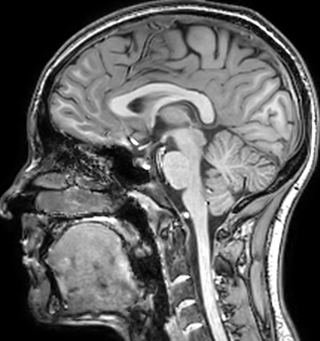

of limiting MWI to the brain, even without the cerebellum, we can now spend about the same amount of time and scan the whole brain and the cervical spinal cord, which is a huge boost for us.” Dr. Rauscher says, “For MWI we perform 3D T2 with 32 or more echoes. This used to take a long time, but with Compressed SENSE we can decrease this to ten minutes for the whole head. Because of the large field of view (FOV) on the readout direction, we even get information from the brainstem, which we previously missed when we were using the GRASE approach. Having the whole head scan is nice because it has spatial resolution, orientation and FOV that are comparable to the standard 3D clinical MS scans, including the FLAIR and 3D T2, and a 3D T1 for brain volume.”

T1 - weighted

Myelin water imaging (echo 1)

T1 - Weighted, Myelin Water Fraction Superimposed

Spinal cord coverage

Smaller, more isotropic voxels

Excellent detail in quantitative maps

Images courtesy of Adam Dvorak, Department of Physics and Astronomy, University of British Columbia